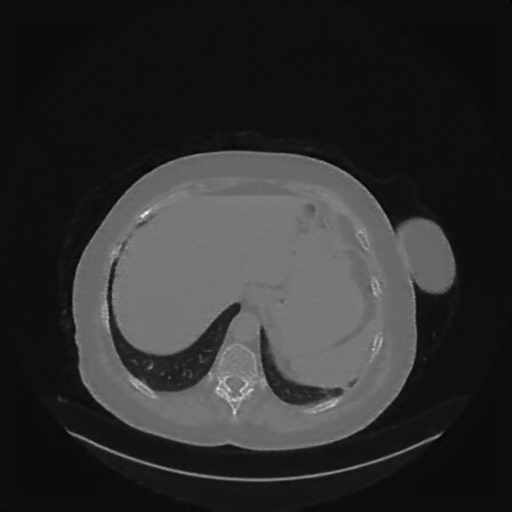

Original NATIVE CT scan (input)

No window - Raw intensity values

Reconstructed NATIVE CT scan (cycle consistency)